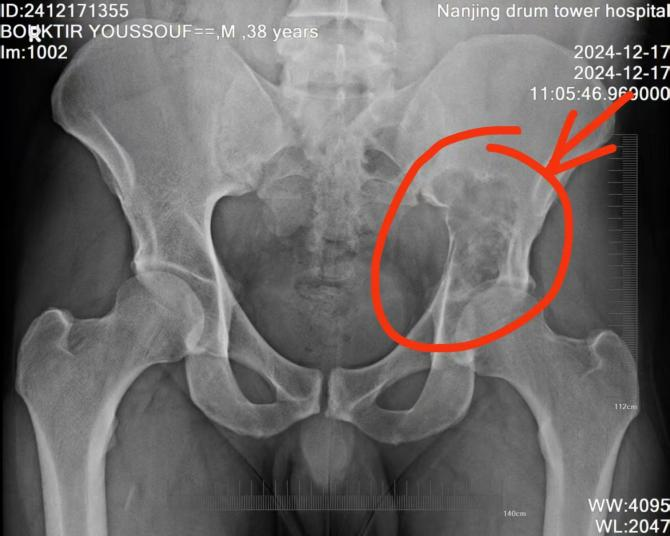

2024年12月19日,BOUKTIR YOUSSOUF来到中国,在南京鼓楼医院接受了磁共振(MR)检查,结果显示左侧髂骨病变,疑为软骨肉瘤。12月23日,经皮穿刺骨活检病理结果显示为非典型软骨源性肿瘤(高分化软骨肉瘤)。结合前期的大量诊断,王守丰主任医师团队根据患者病情,为其制定了详细的个性化手术方案。

手术前后对比